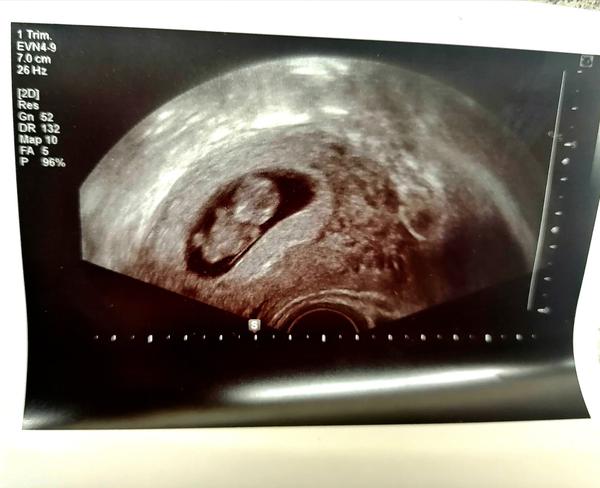

Podělujte se o zkušenosti. Je na ultrazvuku opravdu vidět dvojčata?

Zdravím všechny 🙋♀️,dnes jsem byla na kontrole a jsem 9+3tt. Poslala jsem fotku UTZ švagrové a ona mi gratulovala k dvojčátkám😂 a teď už to tam vidím i já a furt nad tím přemýšlím. Nepoznal by někdo, co je na pravé straně? P. doktorka mi dnes udělala opravdu rychlý UTZ, třeba to mohla přehlédnout. Děkuji za Vaše reakce a přeji krásný zbytek dne ❤️ ❤️ ❤️ ❤️ ❤️ ❤️ ❤️ ❤️ ❤️

@helleen1212 podle mě je miminko jasně jen jedno🤷žádné druhé nikde nevidím..myslím si že kdyby byli dvě doktorka by zrovna tohle nepřehledla a byli by jasně vidět od samého začátku...já sem ale amatér sama mám děťátko jen jedno a na té pravé strane nevidím nic

@helleen1212 to je jedno miminko. Na druhé straně může být konečník (tvůj), kdyby dr trošku posunula sondu ultrazvuku, tak by to šlo vidět lépe.

Ale na tomhle uzv je jen jeden plod 🙂

@helleen1212 Dr není hloupý a vidí dobře.. je tam jedno. Sama jsem dvojčata měla a ultrazvuk s dvojčaty vypadá jinak 😉

@helleen1212 gratuluju k jednomu krásnému mimču 🙂 dvě tam nikde nevidím, jestli přemýšlíš, co je vpravo, tak to může být malý hematom (nebo dva), nějaké zakřivení sliznice, konečník, cokoliv...ale dvě miminka to nejsou🙂

Ultrazvukovy obraz je obraz 2D obraz 3D tělesa, v tomto případě dělohy. To znamená aby bylo vidět, jestli tam není ještě jeden plod , je potřeba,, projet ,, celý organ. Z jeho obrázku ti to nikdo neřekne, druhý plod může být vidět na jinych semenech a podle toho jak se natočí sonda, zachytí se i vedle sebe. Ale doktor to určitě nedělá první den, nehodnotí z jednoho obrszku a kdyby tam byly dvě dutiny, tak ti to řekne 😉

@helleen1212 to je jasné jedno miminko dvě nejsou

To by urcite neprehledla, deloha je jasne ohranicena. Vpravo vypada jako vajecnik.

Děkuji všem holky za uklidnění. 😂 Taky jsem si myslela, že by to viděla p. doktorka, jelikož tam mělo miminko diskotéku 😂 a že by druhé se ani nehlo?

Já teda nevím ale vidím jen jedno miminko

@helleen1212 Ty stíny po stranách můžou být vaječníky, když nejsem těhu, tak doktor sondou vždy vaječníky prohlíží a také to dělá tmavá místa. Ale ohraničená dutina děložní je tam jen jedna a v ní viditelný jeden plod.